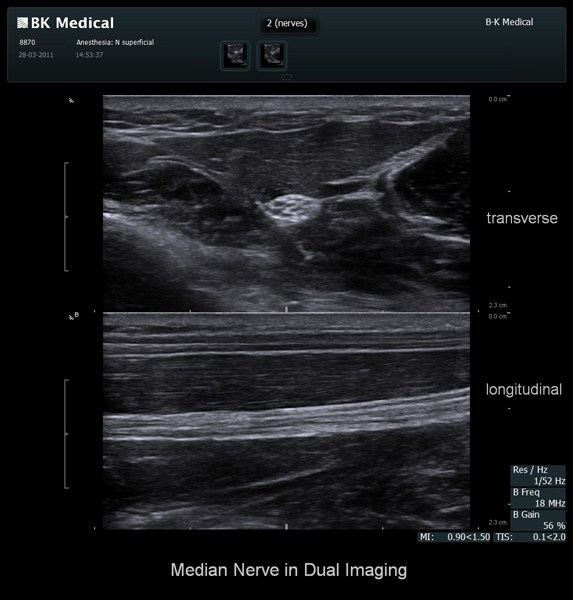

The Flex Focus 400 exp ultrasound system offers premium image quality with fast frame rates for excellent temporal resolution. The system features Automatic Mode Adjustment (AMA) to optimize high resolution B-Mode Imaging when changing modes and depth.

BK Medical offers high-frequency linear transducers, imaging from 18-2 MHz for upper and lower extremities, and curved array abdominal transducer 8820e for special deep nerves or paravertebral/spinal applications. Our transducers provide superb detail that makes it easy to see your needle during procedures.